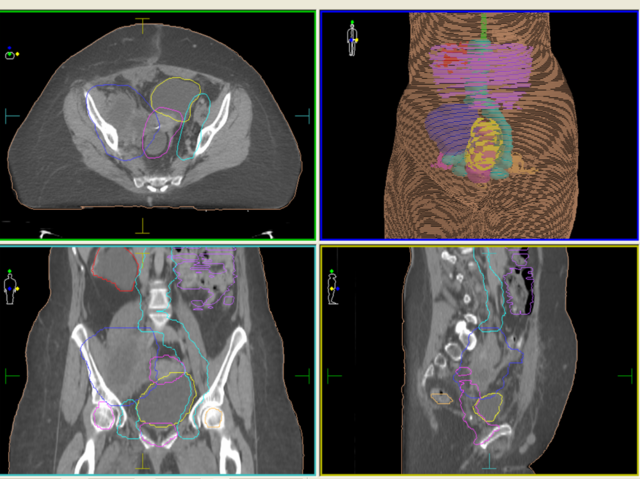

1972 Godfrey Newbold Hounsfield y Allan Mcleod Cormack presentan el primer modelo de tomógrafo computarizado que muestra cortes sagitales, logrando visualizar con más detalle partes internas del cuerpo en especial los tejidos blandos.

1979 Godfrey Newbold Hounsfield y Allan Mcleod Cormack reciben el premio novel por el descubrimiento de la tomografía computarizada.